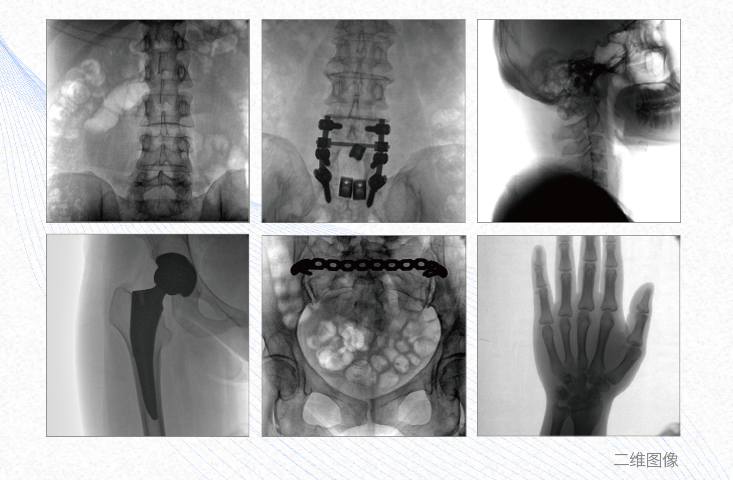

1、脊柱外科

有效重建復雜的脊柱三維模型,提供準確的二維、三維圖像,提高螺釘植入的準確性,縮短手術(shù)時間,減少并發(fā)癥的概率,降低輻射的攝入。

2、創(chuàng)傷外科

例如骨盆骨折內(nèi)固定術(shù),可術(shù)中三維重建髖臼關(guān)節(jié)面,準確定位并植入螺釘,有效縮短螺釘植入的時間和透視暴露時間,減少術(shù)中及術(shù)后并發(fā)癥發(fā)生的概率。

3、關(guān)節(jié)外科

主要應用于肩關(guān)節(jié)、肘關(guān)節(jié)、髖關(guān)節(jié)、膝關(guān)節(jié)的關(guān)節(jié)置換及解剖復位的定位。它可以準確地置入假體,減少輻射時間,降低輻射劑量。

4、截骨矯形外科

例如治療先天性脊柱側(cè)后凸畸形,可有效引導術(shù)者植入后路螺釘并切除半錐體,達到滿意的截骨矯正效果。